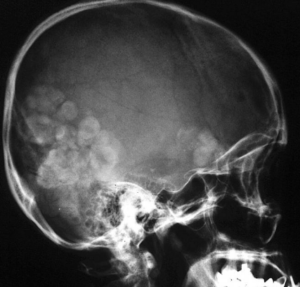

Различают острое и хроническое поражение головного мозга. Для острого характерно внезапное развитие неврологической симптоматики, обычно на фоне легочной патологии. При хроническом нередки эпилептические припадки и стойкие неврологические нарушения; при рентгенографии черепа обнаруживают кальцификаты в виде «мыльных пузырей».